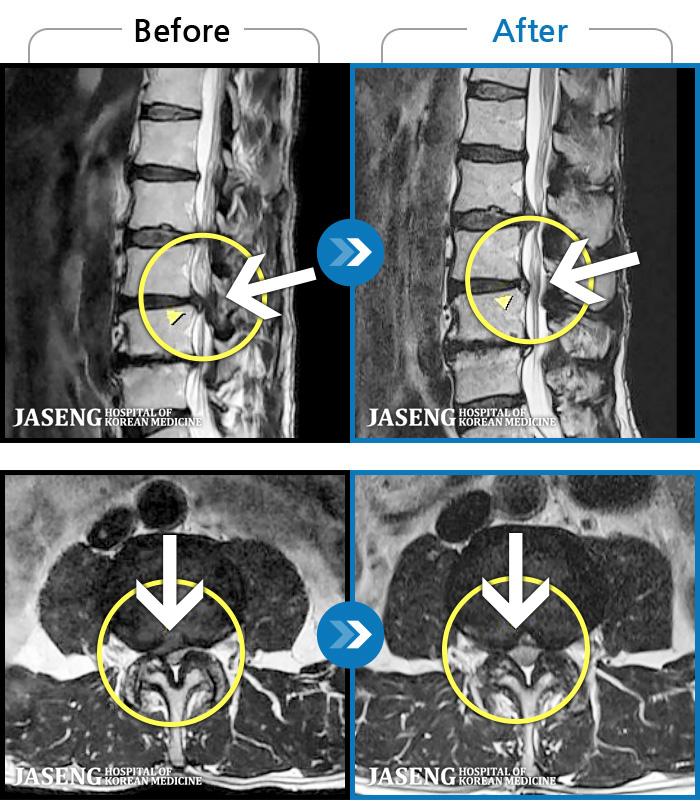

MRI ġ

1,245 MRI ũ ʸ Ȯϼ.